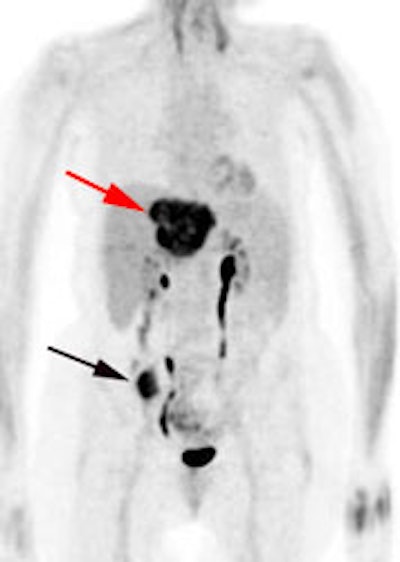

Initial staging for colorectal carcinoma: The patient below presented for evaluation of colorectal carcinoma. The CT scan demonstrated a large liver mass (red arrows) compatible with metastatic disease. The patient's cecal mass (black arrow on PET scan) was not detected on the CT study (white arrow). No other lesions were identified on the PET scan. |

|